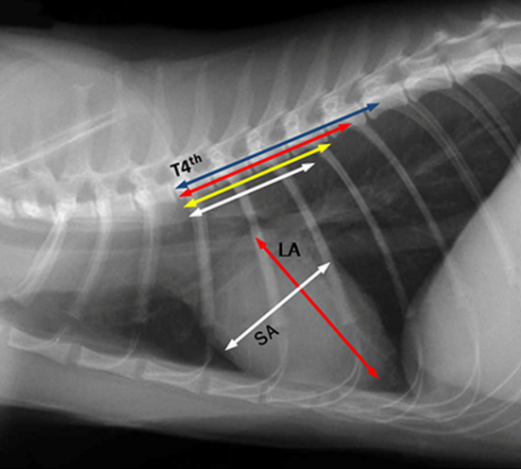

canine and feline VHS : 개와 고양이의 심장 크기평가

In cat : 7.3-8.1